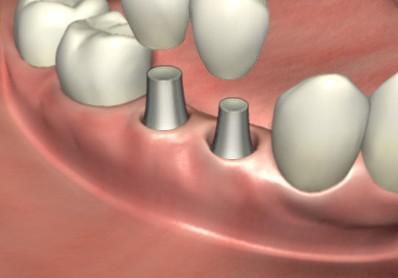

4、软组织成形后用永久基台换下愈合基台,较后安装固定种植牙冠便完成了种植牙手术。